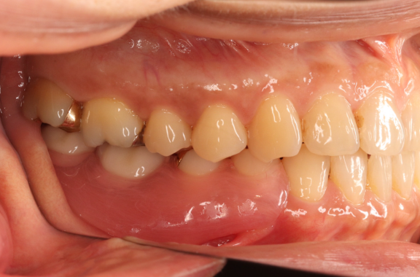

入れ歯の症例

当院で入れ歯治療をされた方の症例をご紹介いたします。

治療前